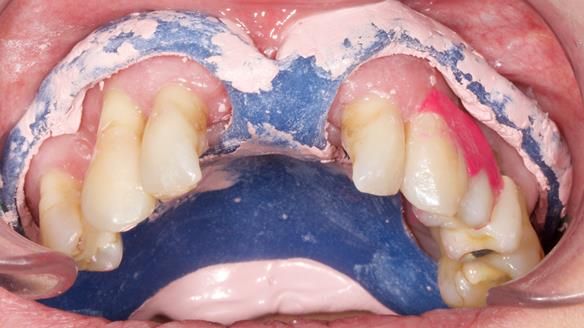

We provided her with an immediate upper denture (Mk 1), followed by a definitive metal-based upper denture (Mk 2). A lower removable partial denture was discussed, to be made only if needed once the upper treatment was complete. However, at review, this wasn’t necessary — Adnana had excellent neuromuscular control and function, even with a shortened dental arch (SDA).

Rowan, Sam Hesketh and Chris Hesketh provided the stunning technical work. I am very lucky to have them.